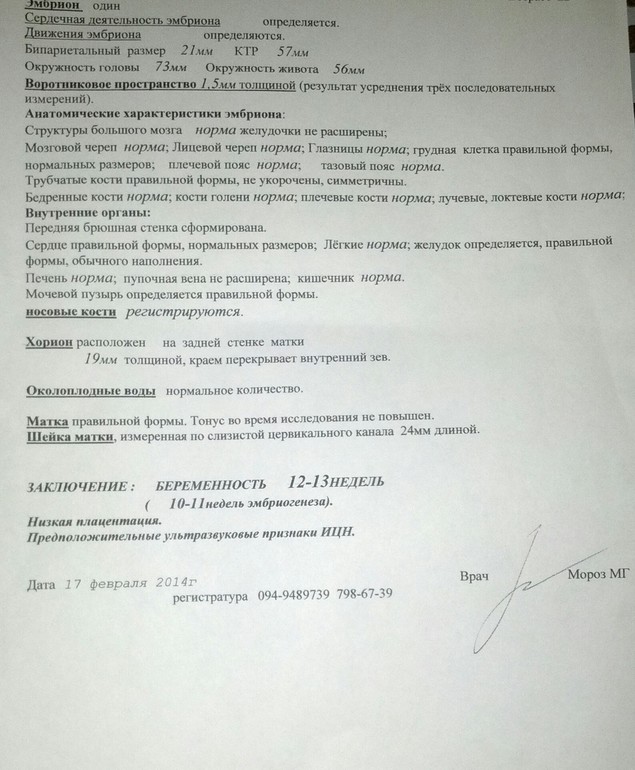

Еле выдержала эти три недели ожидания УЗИ. Сегодня сразу к двум врачам сходили, для пущей верности. Оно того стоило. Посмотрели, как наш головастик для папы танцевал, даже пальчик сосал, этот момент запечатлел нам доктор. Ходили в ЖК и к Морозу, последним остались очень довольны, все очень внимательно смотрел во всех ракурсах, измерял в лучших позах, попутно все подробно объясняя, и фильм нам записал. Разглядел нам пацана, и пипку показал, сказал, вероятность мальчика очень высока, и что на таких сроках редко можно что-то рассмотреть. Срок у меня сегодня 11,4, а плод соответствует 12,4 неделям. Очень переживала по поводу аномалий всяких, но, ттт, все в норме, но моя бурная фантазия обязательно найдет на что переключиться)))